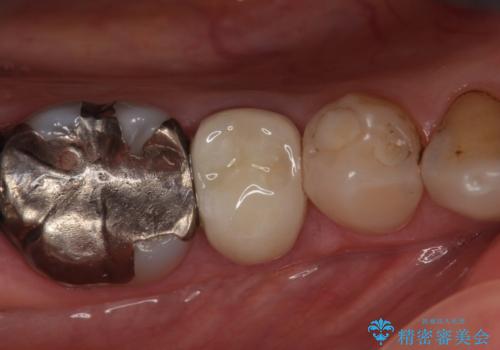

- 右下の歯でものを咬むと違和感があるので診て欲しいといらっしゃった方の症例です。

右下5番目の歯に根尖病変を認めたため、再根管治療を行い、オールセラミッククラウンによる補綴を行いました。

- オールセラミッククラウン…¥100,000、仮歯…¥10,000、ファイバーコア…¥20,000費用は治療当時の料金となります

今回用いたオールセラミッククラウンは、ジルコニアフレームという白い素材の上にセラミックを盛っているため審美性が非常に高いのが特徴です。

またジルコニアは人工ダイヤモンドの材料にも使われているほど高い強度を持っており、そのためオールセラミッククラウンは審美性だけでなく、奥歯やブリッジの補綴も可能とするクラウンです。